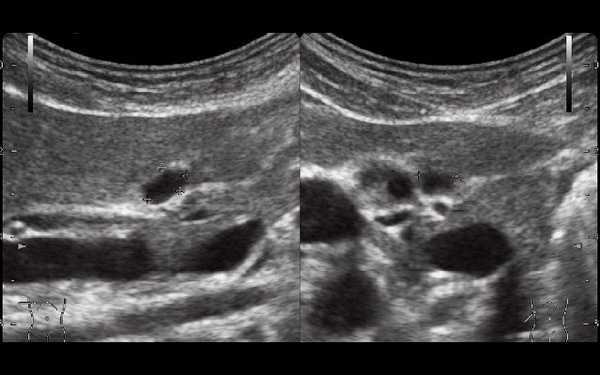

С подозрением на дивертикулит больная была направлена на срочное ультразвуковое исследование (УЗИ) органов брюшной полости, почек и органов малого таза. Исследование было выполнено на современном аппарате конвексным датчиком 3,5 МГц, линейным датчиком 7,5 МГц и эндовагинальным датчиком с переменной частотой 5,0-7,5 МГц с использованием цветового и энергетического допплеровского картирования.

При УЗИ были выявлены диффузные изменения печени и поджелудочной железы, признаки хронического бескаменного холецистита, ангиомиолипома левой почки (без динамики за несколько лет), состояние после экстирпации матки с придатками. В левой подвздошной области соответственно зоне максимальной пальпаторной болезненности на протяжении 9 см отмечалось утолщение стенок толстой кишки до 6-7 мм (рис. 1). Перистальтика кишки отсутствовала, гаустрация была слабо выражена, при этом визуализировалось несколько болезненных при надавливании датчиком выпячиваний пониженной эхогенности, размером от 7 до 20 мм (рис. 2, а, б) с тонкой стенкой до 0,9-1,1 мм и наличием в некоторых из них фрагментов кишечного содержимого и газа (рис. 3, а, б).

Рис. 1. Эхографическая картина дивертикулита. Трансабдоминальное исследование линейным датчиком 7,5 МГц.

"Симптом пораженного полого органа".

Рис. 2. Эхографическая картина дивертикулита. Трансабдоминальное исследование линейным датчиком 7,5 МГц.

а) Продольный срез.

б) Поперечный срез.

Рис. 3. Эхографическая картина дивертикулита. Трансабдоминальное исследование конвексным датчиком 3,5 МГц.

При трансвагинальном УЗИ (рис. 4) также визуализировался фрагмент толстой кишки с утолщенными гипоэхогенными стенками и несколькими округлыми дивертикулами до 1 см в диаметре. Контуры одного из дивертикулов были неровными, он имел звездчатую форму. Отмечались утолщение и повышение эхогенности околокишечной жировой клетчатки по сравнению с контралатеральной стороной. При осмотре в режиме УЗ ангиографии утолщенная стенка кишки и дивертикулы были аваскулярными, окружающая клетчатка - гиперваскулярной.

Рис. 4. Эхографическая картина дивертикулита. Трансвагинальное исследование конвексным датчиком 7,5 МГц.